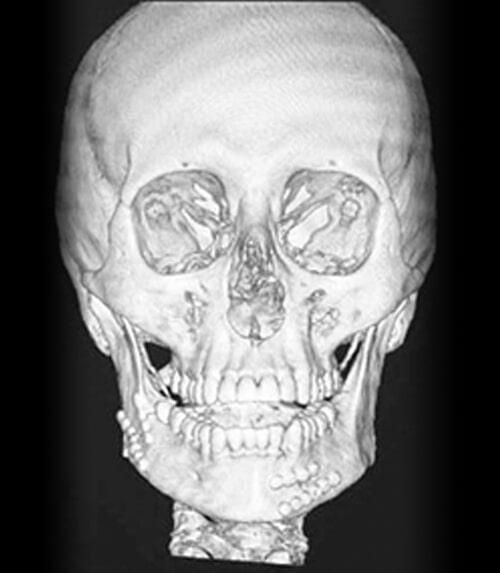

FRACTURA DE ORBITA,

MAXILAR Y MANDÍBULA

Si tienes alguna fractura maxilar y/o mandibular, o te dijeron que te fracturaste, danos la oportunidad de valorarte y brindarte opciones de tratamiento para un pronta recuperación